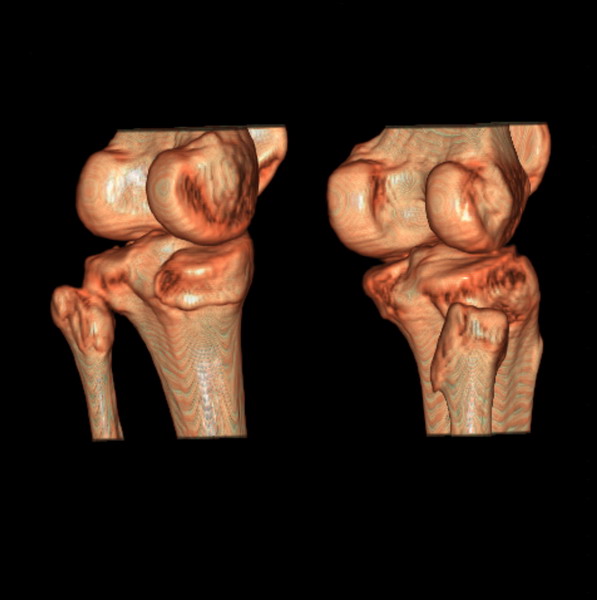

标题: CT21917:右腓骨小头是否骨软骨瘤? [打印本页]

标题: CT21917:右腓骨小头是否骨软骨瘤?

女、43.

不是骨软骨瘤,“牵拽征”,正常变异。有平片吗?

正常变异,“牵拽征”,比目鱼肌牵拽.

比目鱼肌附着点